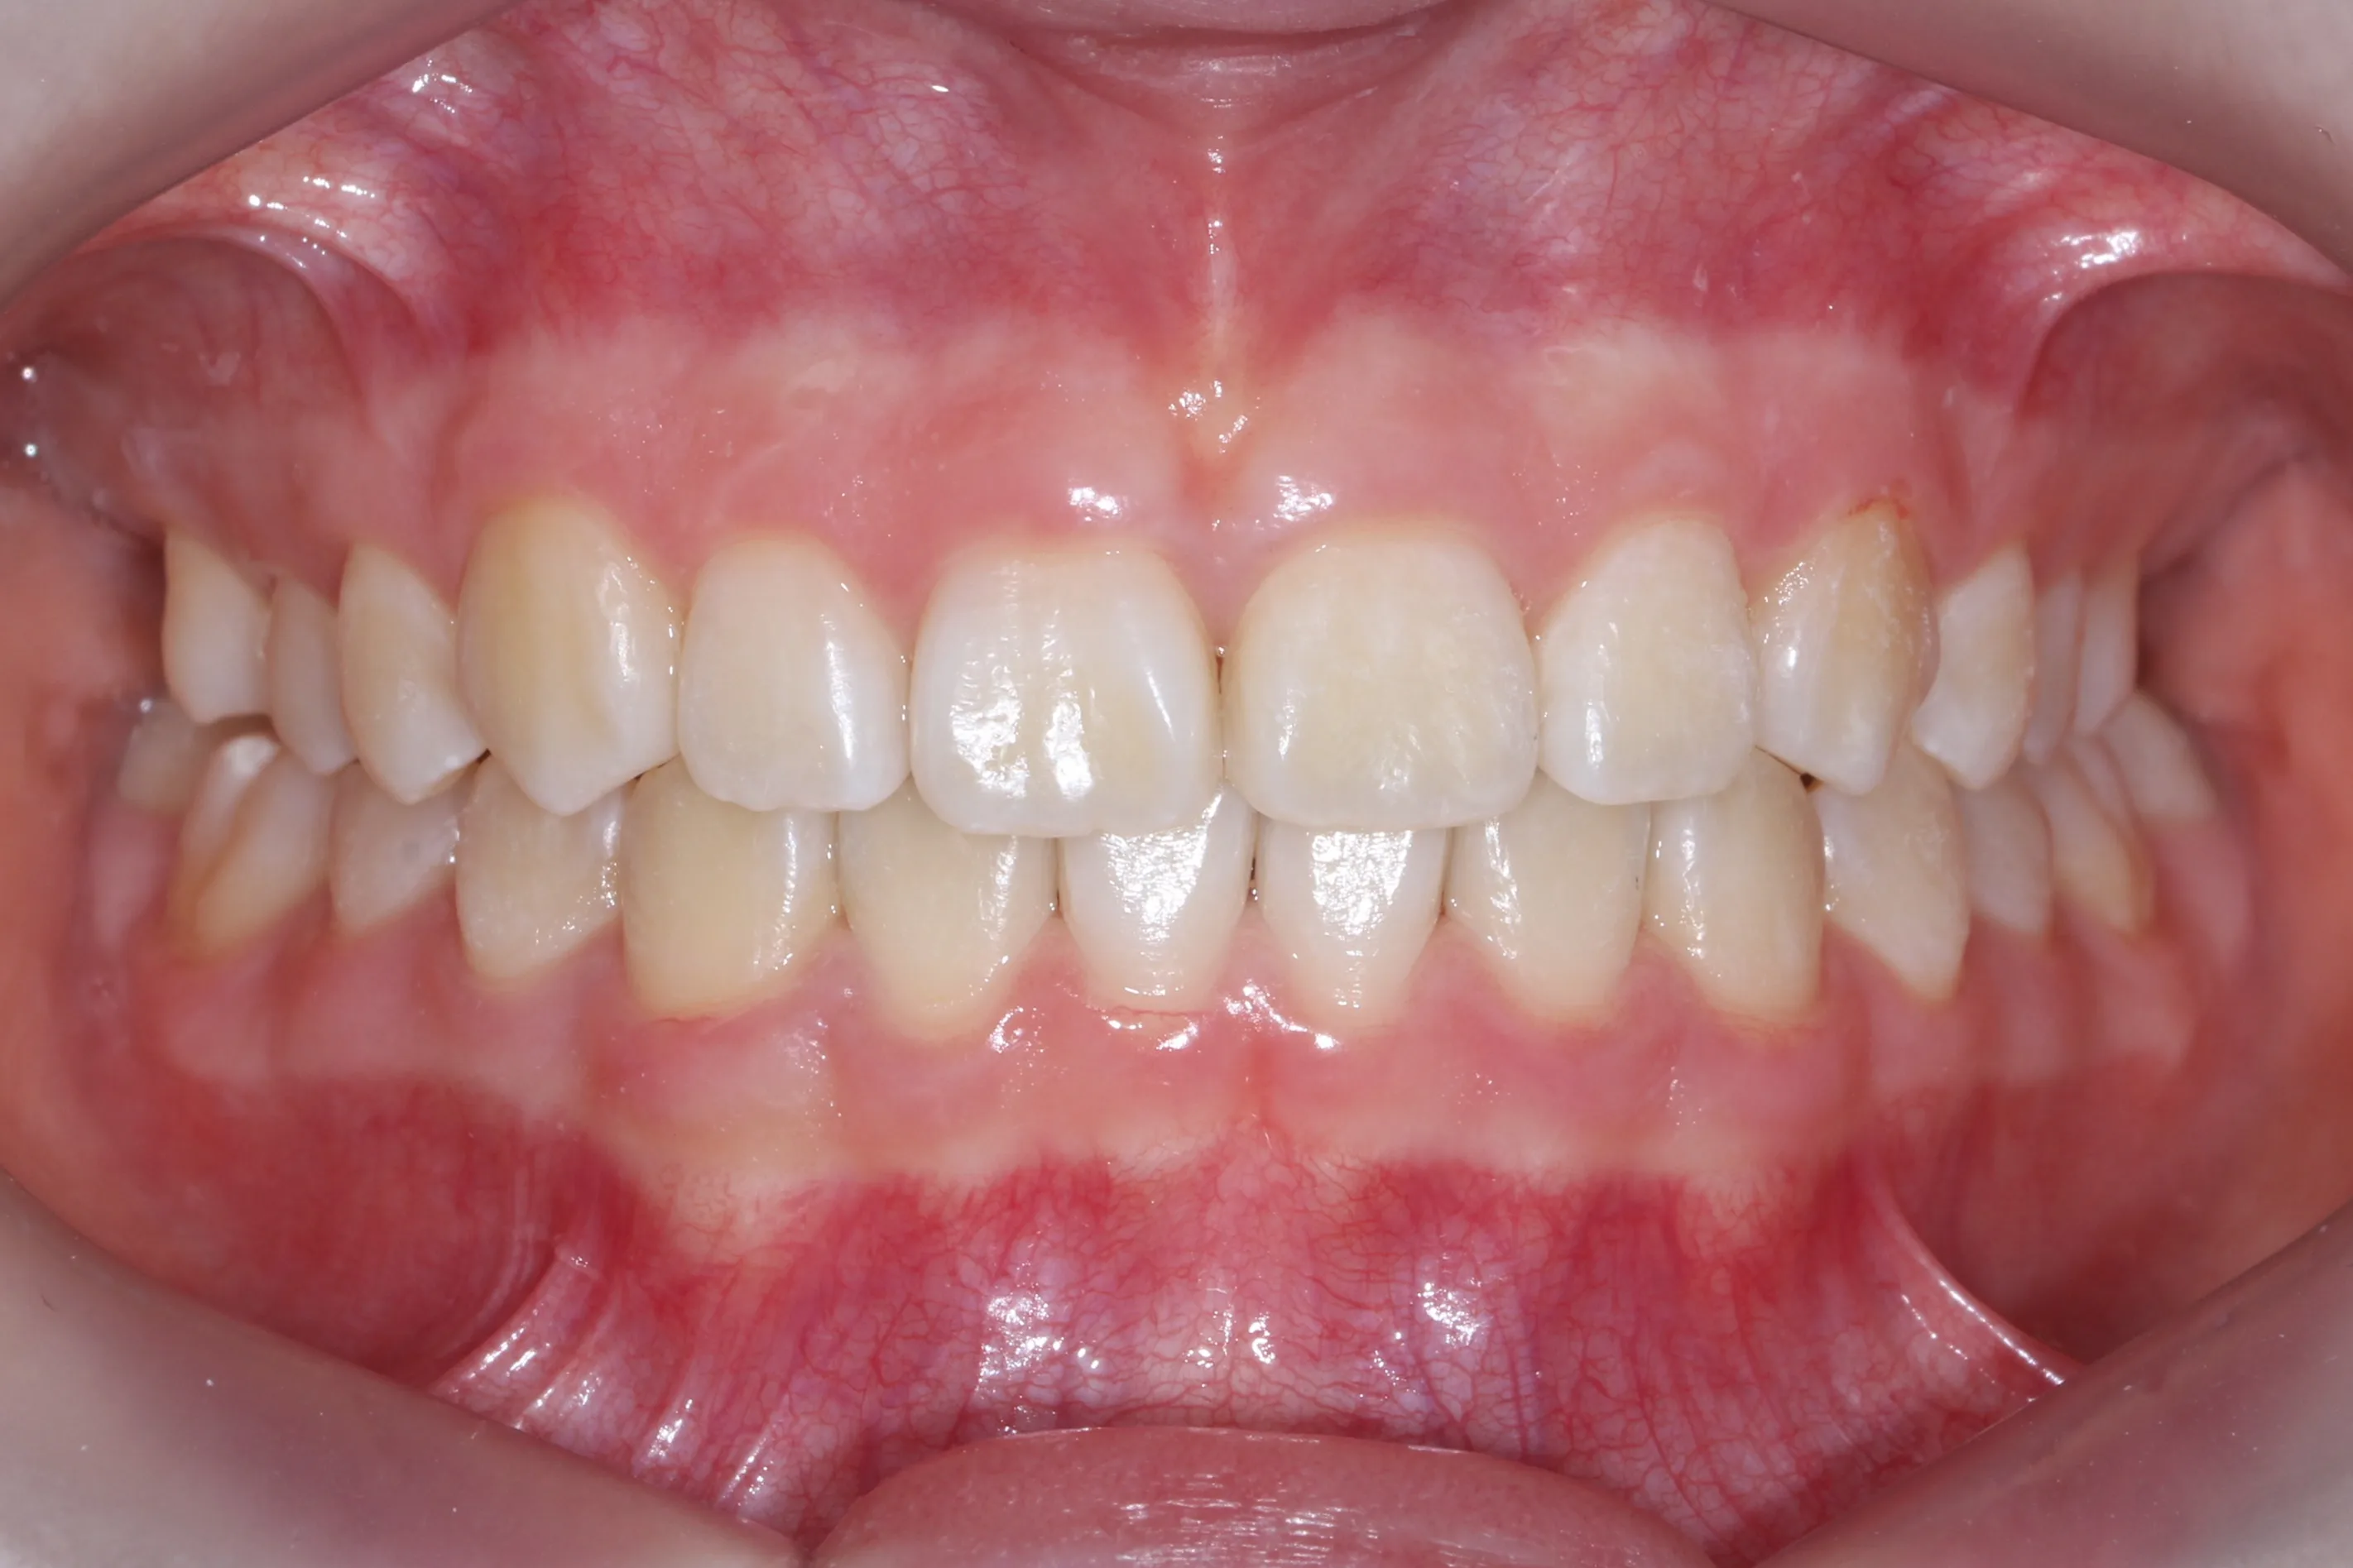

2년 7개월의 치료 과정을 거치며 환자분의 협조도 덕분에 안모 프로파일과 교합이 안정적으로 개선되었습니다. 성장기라고 해서 무조건 교정이 어려운 것은 아닙니다. 적절한 시기에 맞춤형 장치를 선택한다면 골격적 불균형을 효과적으로 바로잡을 수 있습니다.